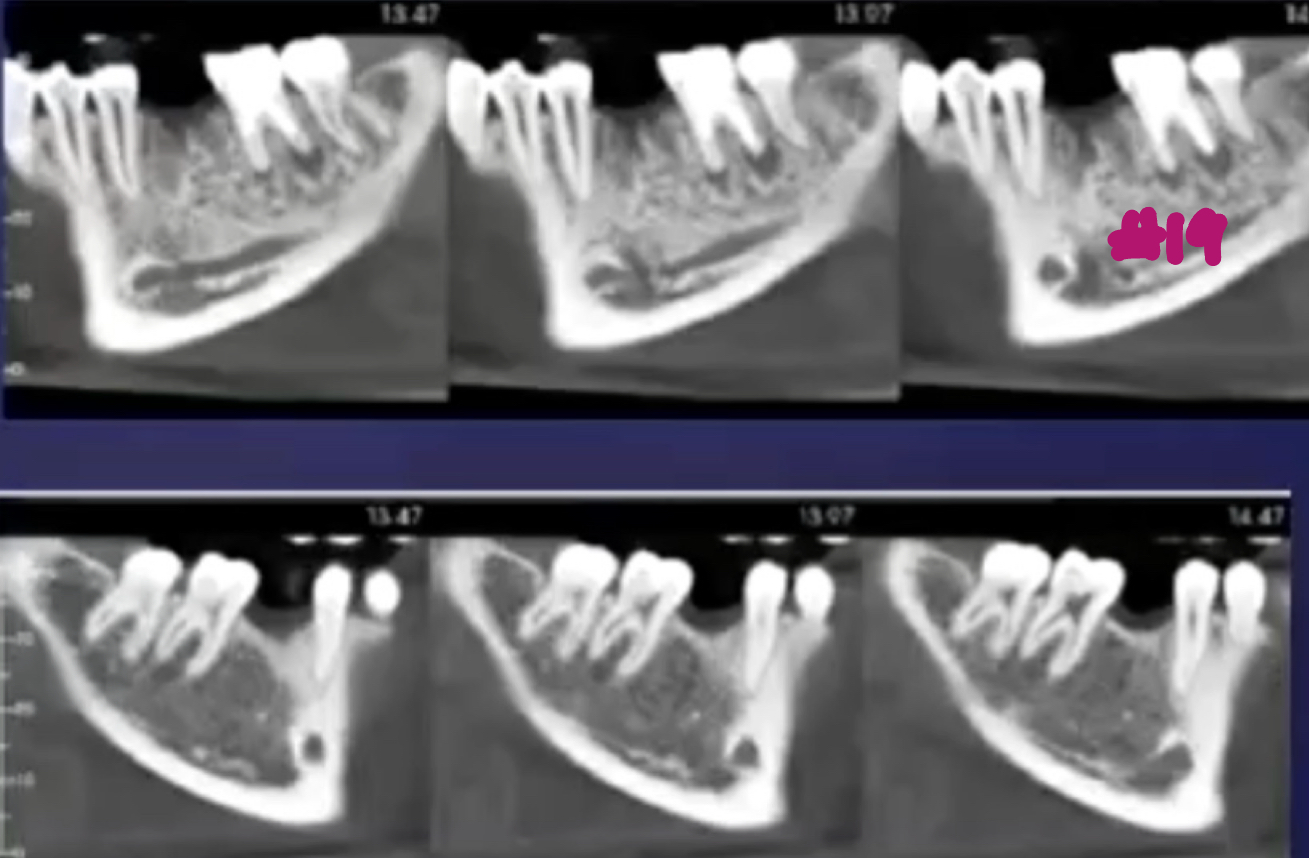

what are the alterations in trabecular bone pattern and marrow spaces of periapical inflammatory diseases?

thicker trabeculae and increase in numberÂ

what are some effects of periapical inflammatory disease on surrounding structures?

bone deposition

alteration in trabecular bone pattern and marrow spaces

periosteal new bone formation

perforation of bone border

halo sign

elevation/displacement of floor f maxillary sinus